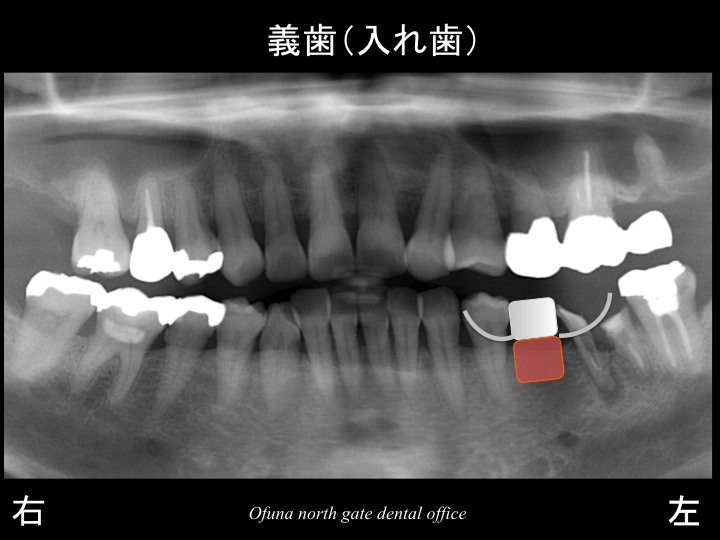

まずは、義歯(入れ歯)です。

義歯(入れ歯)の利点、欠点は以下のようになります。

利点

1.型を取れば、1週間程度で義歯が完成するため、治療期間が短い!

2.保険が適応される!

今回のようなケースの場合 約5.000円程度です。(保険3割負担の方)

3.歯を削る必要性がない!

欠点

1.取り外し式のため、わずらわしい!

2.義歯の形(大きさ)があるため、違和感が非常に強い!

3.保険の義歯の場合、義歯を固定する金属の金具がつくため、審美的に問題がある!